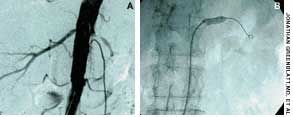

A 73-year-old man with a history of long-standing essential hypertension, congestive heart failure, mild renal insufficiency, atrial fibrillation, and a mitral valve replacement presented with refractory hypertension. Renal angiography was performed. A 99% stenosis in the left renal artery (A) was corrected by balloon angioplasty (B) and stent deployment (C). A second renal angiogram after stent implantation revealed excellent flow to the distal vessels (D).

Images courtesy of Jonathan Greenblatt, MD, Jeffrey Guller, MD, and Robert A. Phillips, MD.